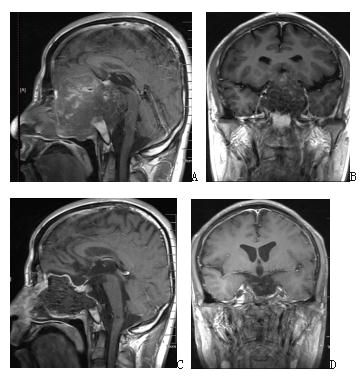

3. Craniopharyngioma

Transnasal endoscopic surgical resection is preferred for most craniopharyngiomas. It is minimally invasive, with a mild reaction, slight damage to vision and endocrine, and rapid patient recovery.

Figure 3. A and B Enhanced MRI before surgery suggest suprasellar craniopharyngioma; C Intraoperative screenshot suggests complete resection of the tumor, which can be seen in the three ventricles and the superior port of the midbrain aqueduct; D and E Enhanced MRI after endoscopic transnasal surgery, suggesting complete resection of the tumor.